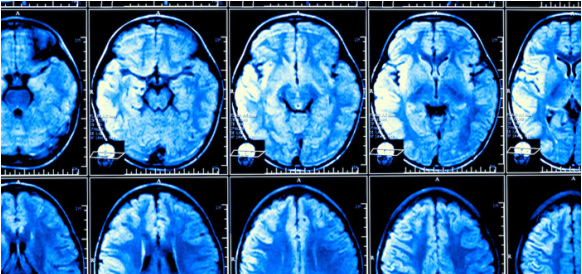

据了解,该研究早在1948年就已启动,总共由5209位年龄在30~62岁的参与者组成,持续至今已有75年,还有二代、三代的参与者,所有受访者均无卒中史或痴呆史,且都做过CT、磁共振成像(MRI)等技术,平均年龄为57.4岁。

UC Davis Health的研究人员对比了1930年代出生的人和1970年代出生的人的MRI数据,结果发现其大脑体积逐十年递增,增加了约6.6%;大脑皮层表面积(脑容量的另一个主要指标)显示出更明显的逐十年增加,增加了约15%。

此外,受试者的白质、灰质和海马体(涉及学习和记忆的大脑区域)等大脑结构的大小,在对比1930年代出生的参与者和1970年代出生的参与者时也有所增加。